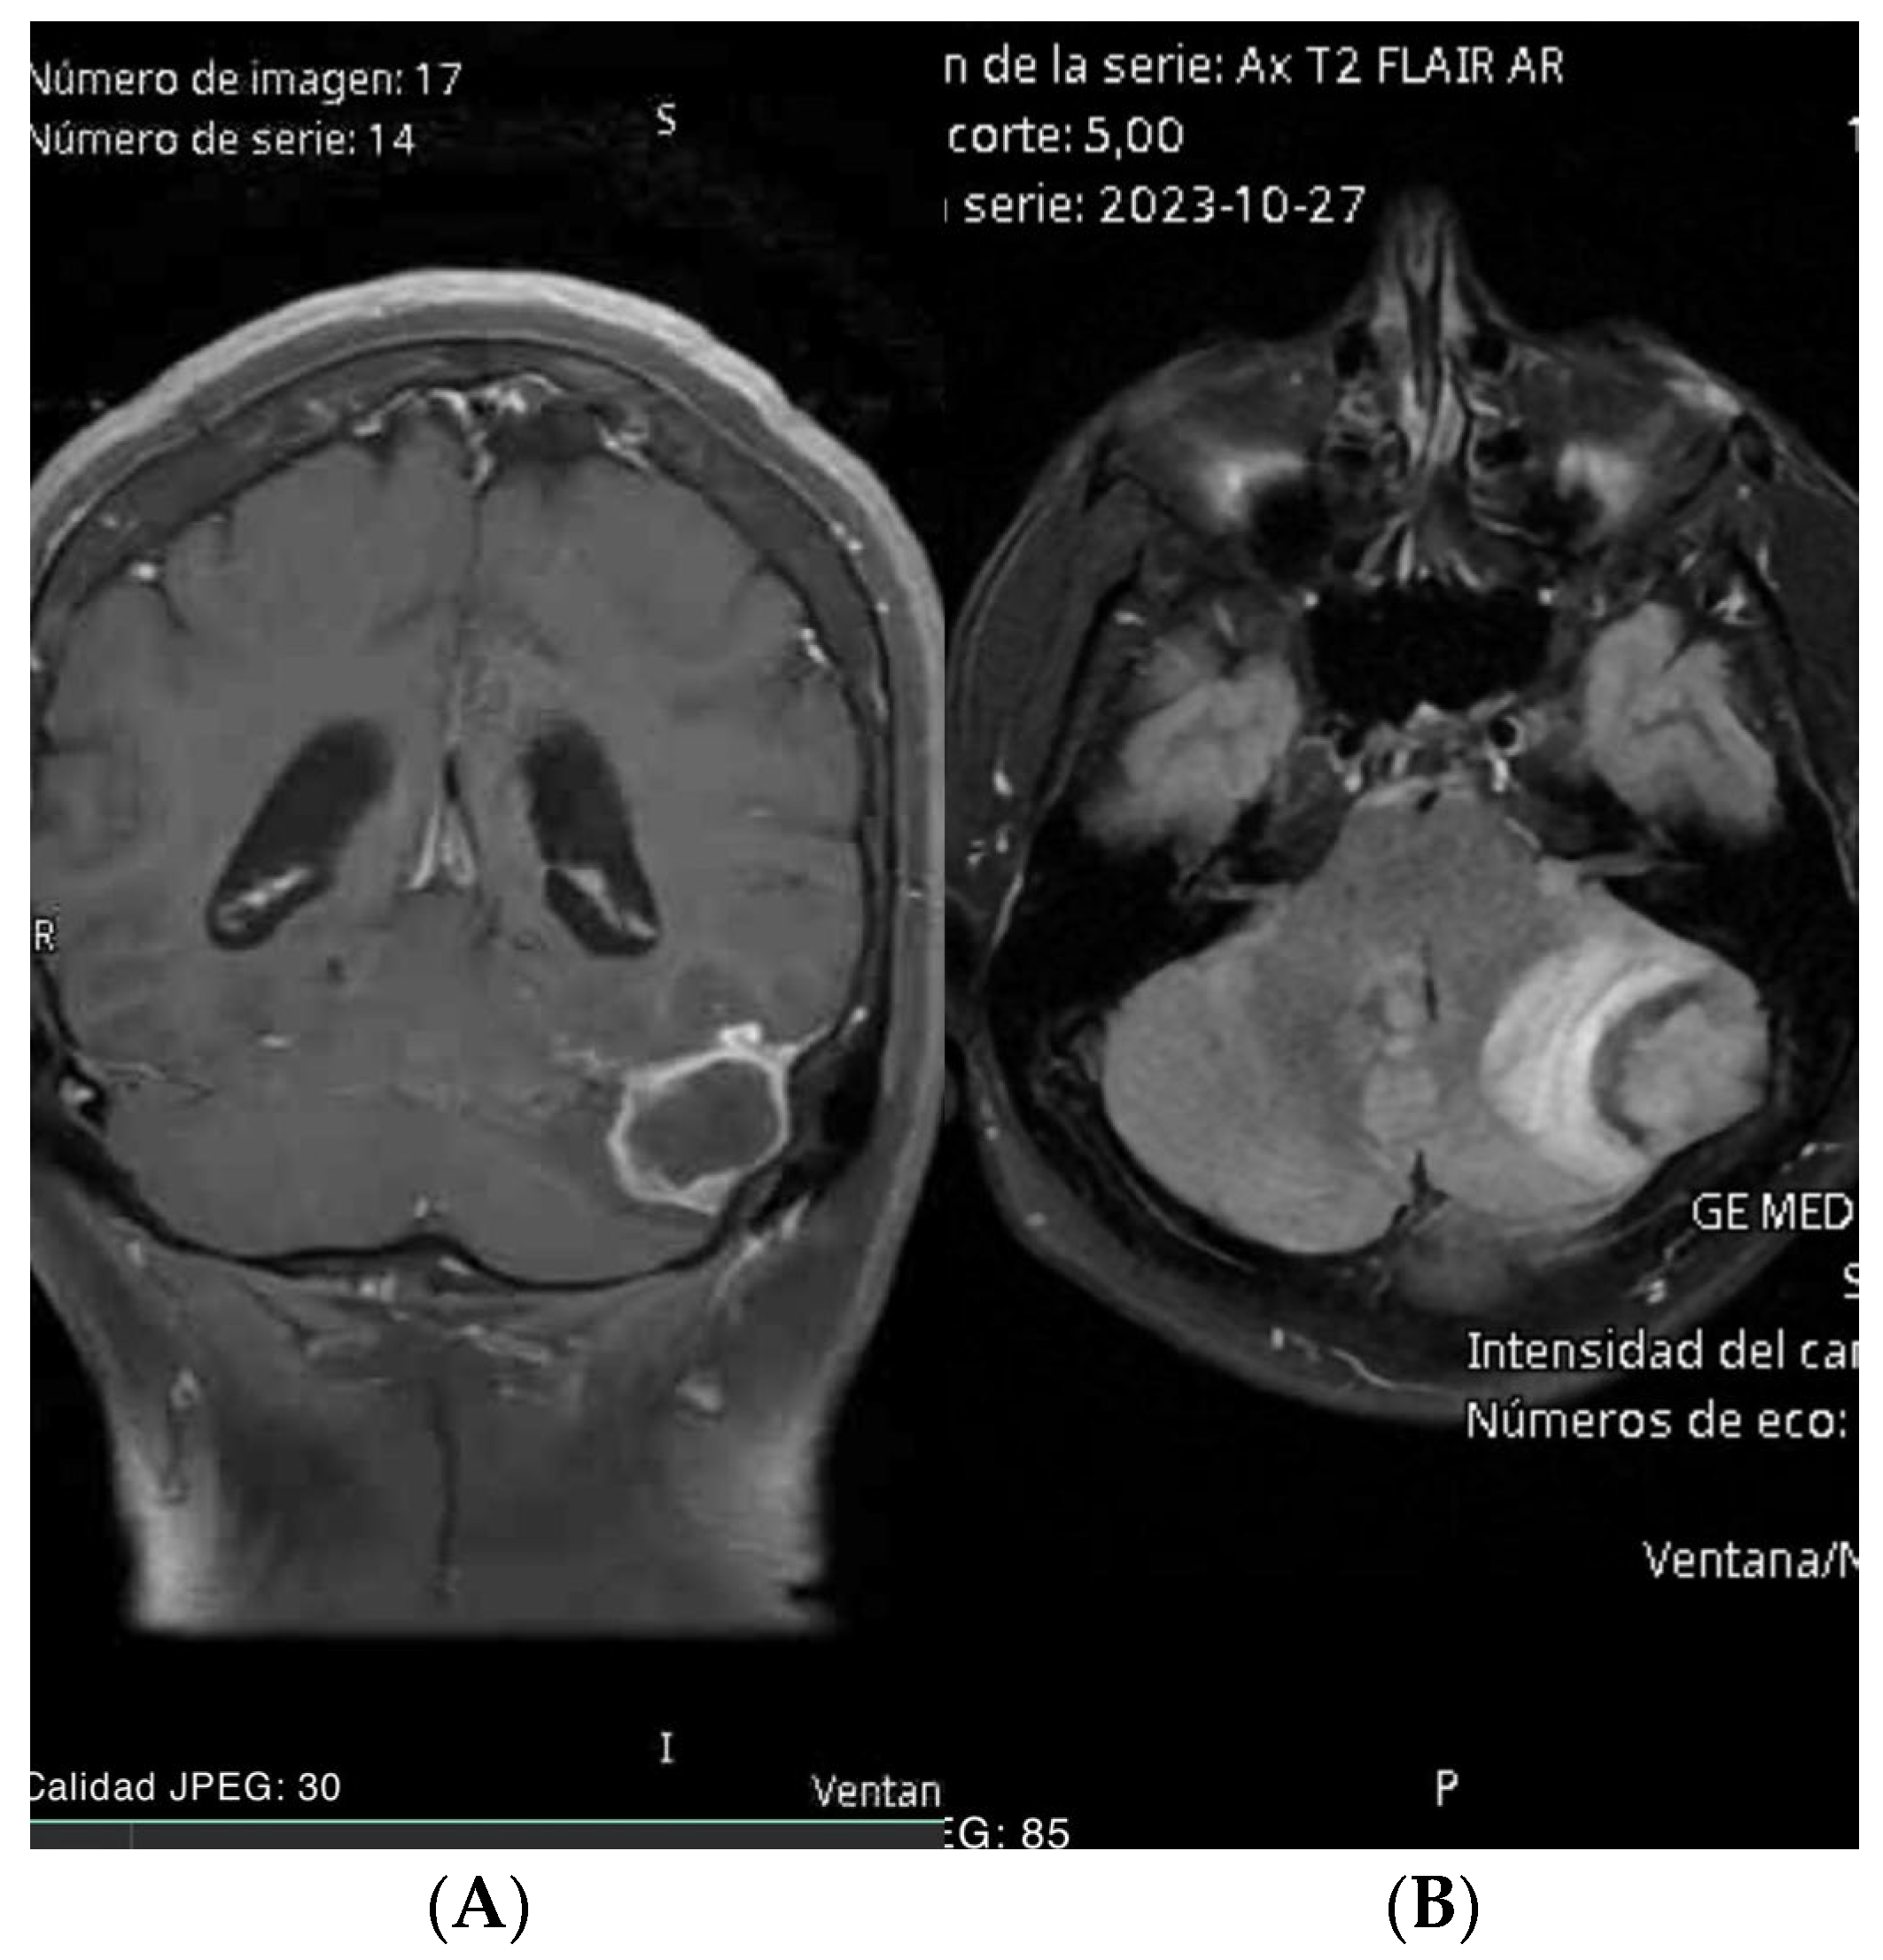

- Case 1: The AR-assisted retrosigmoid approach facilitated an 80% subtotal resection of a complex infratentorial meningioma, resulting in significant symptomatic relief and minimal postoperative complications. This underscores the potential of AR to enhance surgical outcomes in challenging anatomical regions (on the sigmoid and transverse sinuses). (Figure 1 and Figure 2). The patient’s rapid recovery and favorable outcome further emphasize the clinical advantages of AR-guided surgery.